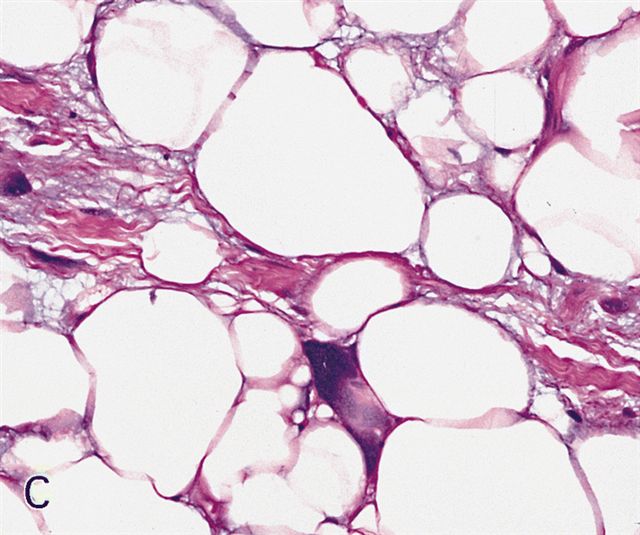

Microscopic (histologic) images

Contributed by Michael Clay, M.D., Melanie Bourgeau, M.D. and AFIP

Metaplastic change:

Microscopic (histologic) description

- Depends on subtype, generally composed of mature fat with variably sized adipocytes and bands of fibrotic stroma containing spindle cells with enlarged, hyperchromatic nuclei

- Lipoma-like subtype

- Most common subtype

- Scattered atypical cells may be diffuse or exceedingly rare

- Frequently contains lipoblasts

- Grossly, can be indistinguishable from lipoma

- Nuclei with sharply outlined vacuoles (Lochkern cells) are enlarged and can appear hyperchromatic but are normal adipocytes cut in cross section

- These do not qualify for the diagnosis; the same goes for atrophic skeletal muscle fibers, which can simulate atypia on an otherwise typical lipoma

- Lipoblasts are neither necessary nor sufficient for diagnosis

- When present they are generally multivacuolated versus the signet ring lipoblasts commonly seen in myxoid liposarcoma